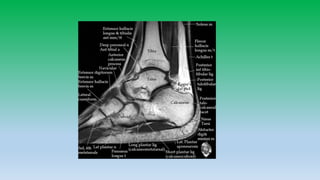

Posterior ankle tendons:

• Achilles and plantaris tendons are located in midline of posterior ankle and is

largest tendon in the body, diffusely low in signal intensity. Usually has flat or

concave anterior margin on axial images. Becomes convex when diffusely

thickened. Normally tendon measures 7 mm in AP-diameter.

• Does not have tendon sheath so cannot have tenosynovitis, but have paratenon

so Para-tendinitis can occurs. Paratenon is seen as thin line of intermediate signal

intensity on axial images.

• Plantaris lies anteromedial to Achilles tendon with high signal intensity fat plane

between.

• Tear of Achilles tendon occurs 4cm above the calcaneus insertion or at

musculotendinous junction.

• Retro-calcaneal bursa is located b/w the tendon and posterior aspect of

calcaneous, whereas tendoachilles bursa is located posterior to tendon in

subcutaneous fat.

• 15. Posterior ankle tendons: • Achilles and plantaris tendons are located in midline of posterior ankle and is largest tendon in the body, diffusely low in signal intensity. Usually has flat or concave anterior margin on axial images. Becomes convex when diffusely thickened. Normally tendon measures 7 mm in AP-diameter. • Does not have tendon sheath so cannot have tenosynovitis, but have paratenon so Para-tendinitis can occurs. Paratenon is seen as thin line of intermediate signal intensity on axial images. • Plantaris lies anteromedial to Achilles tendon with high signal intensity fat plane between. • Tear of Achilles tendon occurs 4cm above the calcaneus insertion or at musculotendinous junction. • Retro-calcaneal bursa is located b/w the tendon and posterior aspect of calcaneous, whereas tendoachilles bursa is located posterior to tendon in subcutaneous fat.